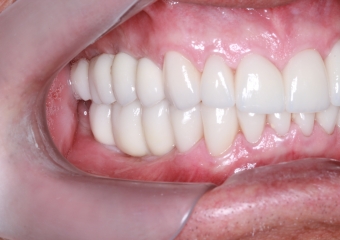

Facetas e dentes em porcelana sobre implantes

Intra oral esquerda final